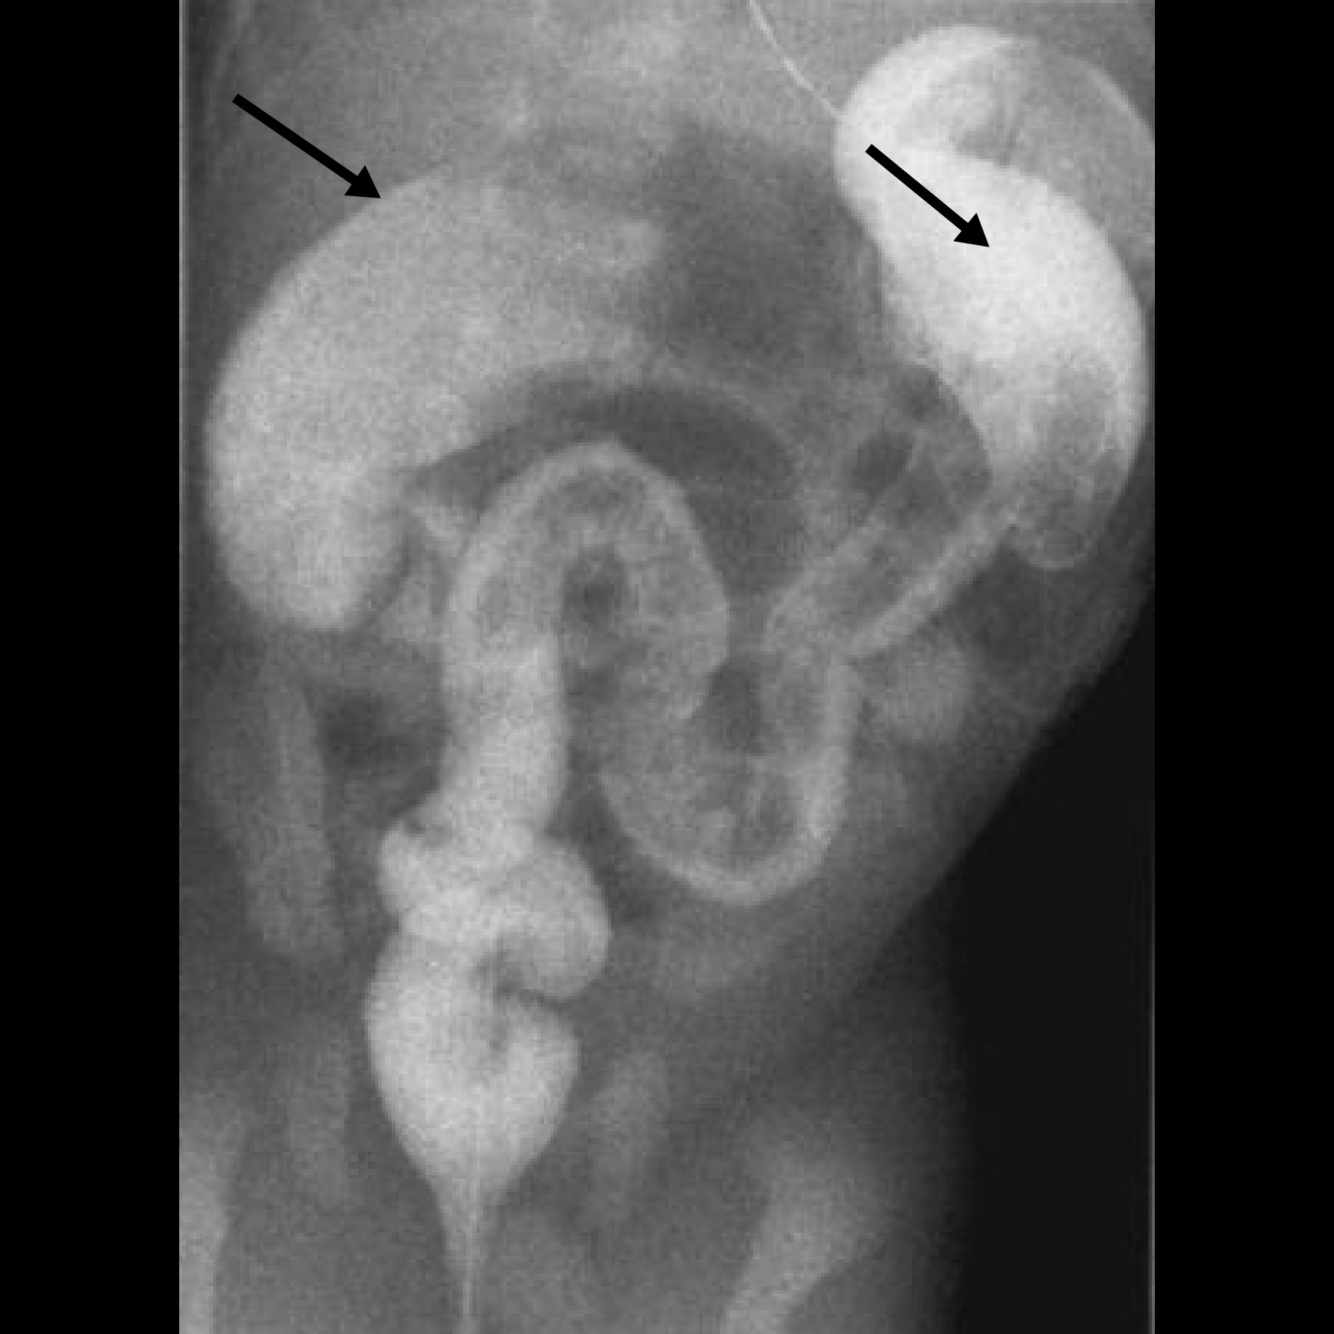

Hirschsprung disease: On barium enema study, she has proximal colonic dilatation